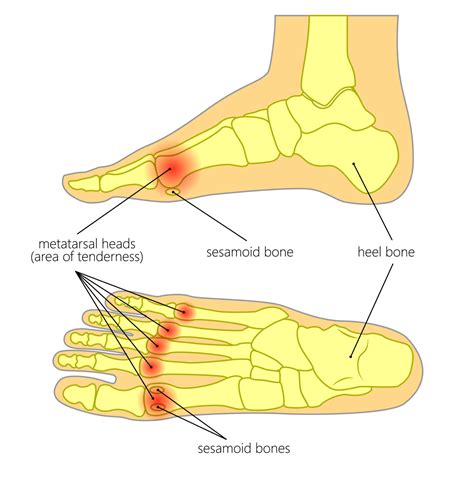

• Pain and Tenderness: Persistent pain and tenderness in the ball of the foot or at the base of the toes.

• Swelling: Inflammation and swelling around the Mtp joint.